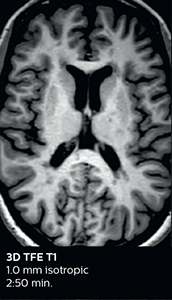

Ingenia Elition 3.0T with Compressed SENSE

3D FLAIR (with Compressed SENSE)

3D FLAIR

1.0 x 1.0 x 1.0 mm*

2:50 min.

3D TSE T1w (with Compressed SENSE)

3D TSE T1w

2:10 min.

*true voxel size, without interpolation

Improving scan time and/or spatial resolution

A two year follow-up scan of a CPA meningioma using both Ingenia 3.0T without CS and Ingenia Elition 3.0T with Compressed SENSE allows for a nice comparison to demonstrate the protocol improvements achieved on the Elition: 3D FLAIR has a shortened scan time, improved SNR and still the same spatial resolution. BrainView (3D T1 TSE) has improved spatial resolution and SNR with shortened scan time. For 3D T2 Drive the spatial resolution has been improved. 3D THRIVE used to have an interpolated 0.8 mm slice thickness, but true thickness at 1.6 mm, so that axial slices displayed a decent quality, but reformats were suboptimal.

Compressed SENSE is used on Elition to improve spatial resolution and reduce the non-interpolated slice thickness to allow smoothly reformatted images. Total scan time (adding SmartBrain and an additional b2000 diffusion) was 13:19 on Ingenia, and is now reduced to 10:42 on Ingenia Elition.